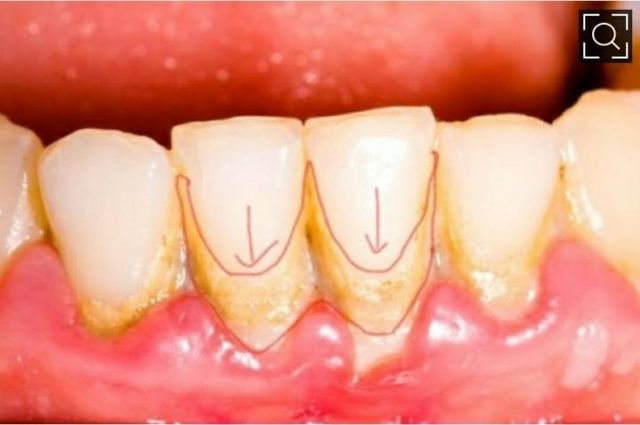

치아 사이도 사이지만

잇몸과 치아 사이에는 잘 보일꺼임

치과사진에서 가져옴

아래 하얀 부분이 치석이야

담배피면 치석 갈색 검은색임.

오래되어도 치석 검게 변함.